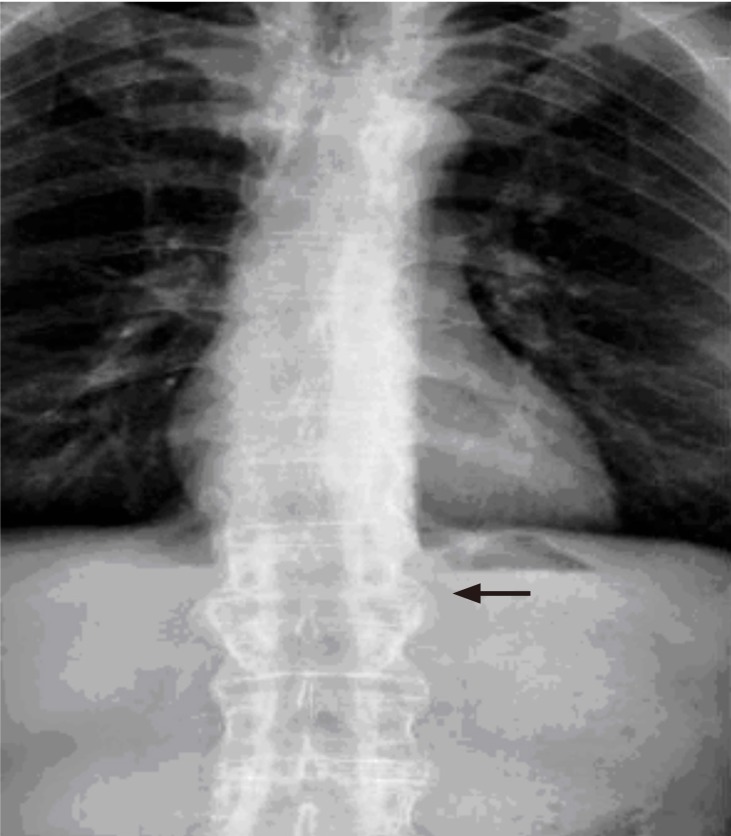

Figure 2

Bamboo spine appearance in the thoracolumbar graphy (shown by the arrow).

Imaging studies revealed SI joint ankylosis and whiskering sign in pubic bones with simple pelvic radiography (Fig. 1). A bamboo spine appearance was present with simple thoracolumbar radiography (Fig. 2). Osteophytes were observed at the anterior corners of vertebra corpuses at C4-5 and C7-T1 levels with lateral cervical radiography (Fig. 3). Esophagography with barium revealed compression of the esophagus due to osteophytes. Cervical computed tomography, performed to localize the osteophytes and for differential diagnosis, revealed fusion between the C5-C6-C7 corpuses with prominent osteophyte formation anteriorly on the left at the C7-T1 level. This formation compressed the esophagus (Fig. 4). Cervical magnetic resonance imaging (MRI) was performed to rule out factors originating from soft tissues as causes of dysphagia. A large osteophyte formation on anterior vertebra corpuses at the C7-T1 level, which caused compression on esophagus, was defined in the cervical MRI (Fig. 5).